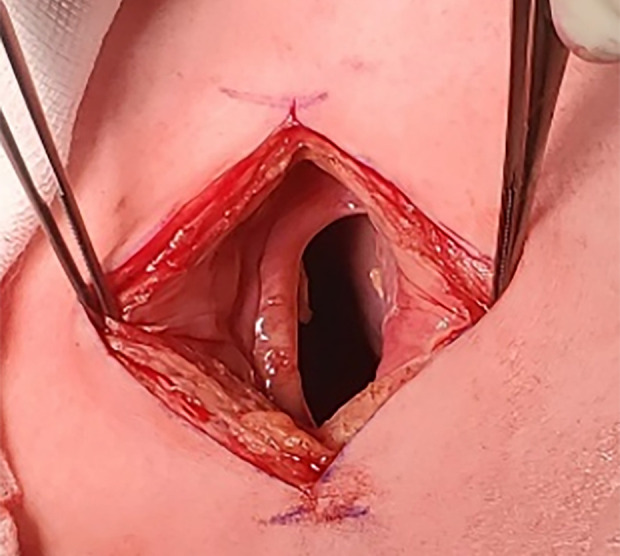

背景胸腔镜解剖肺切除术后,胸壁疝和残余胸膜间隙是已知的并发症。一些胸壁疝的危险因素已被描述;然而,残余胸膜间隙从未被描述为其中之一。我们报告的2例病例表明,术后残留的空气空间可能是胸壁疝的一个新发现的危险因素。病例报告:病例1:一名71岁男性在三孔胸腔镜下左下肺叶切除术治疗早期非小细胞肺癌1周后,在第4肋间切口处发生胸壁疝。他没有任何已知的术后胸壁疝的危险因素,但他的术后过程因残余胸膜间隙而复杂化。病例2:一名60岁男性,因早期非小细胞肺癌行三孔胸腔镜右根尖上叶节段切除术5个月后,在第四肋间切口术后出现胸壁疝。未发现术后胸壁疝的危险因素;然而,她的术后过程也因残余胸膜间隙而复杂化。结论胸膜残留气体通过胸腔镜切口可能阻碍伤口愈合,有利于胸壁疝的发生。在有风险的患者中采用视频辅助胸外科切口闭合技术可能有助于预防术后胸壁疝。这些病例强调了残留胸膜间隙可能是术后胸壁疝的一个新发现的危险因素,并提出了潜在的预防措施。

BACKGROUND Chest wall hernia and residual pleural space are known complications after thoracoscopic anatomical lung resection. Some risk factors for chest wall hernia have been described; however, residual pleural space has never been described as one of them. We present 2 cases suggesting that postoperative residual air space can represent a newly identified risk factor for chest wall hernia. CASE REPORT Case 1: A 71-year-old man developed a postoperative chest wall hernia at the fourth intercostal incision level 1 week after a 3-port thoracoscopic left lower lobectomy for early-stage non-small cell lung carcinoma. He was not known to have any described risk factors for postoperative chest wall hernia, but his postoperative course was complicated by a residual pleural space. Case 2: A 60-year-old man developed a postoperative chest wall hernia at the fourth intercostal incision level, diagnosed 5 months after a right apical upper lobe segmentectomy by 3-port thoracoscopy for early-stage non-small cell lung carcinoma. She was not known to have any risk factors for postoperative chest wall hernia; however, her postoperative course was also complicated by a residual pleural space. CONCLUSIONS We suggest that air flow through the thoracoscopic incision, due to residual pleural air, could impede wound healing and favor chest wall hernia. Adaptation of the closure technique for video-assisted thoracic surgery incisions in patients at risk may help prevent postoperative chest wall hernias. These cases highlight the possibility that residual pleural space could be a newly identified risk factor for postoperative chest wall hernia and propose potential preventive measures.